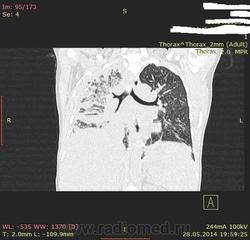

Здравствуйте , коллеги.Нужна помощь.Больная 1983 г .Болеет в теч 1месяца заболела остро после переохлаждения ,лечилось стацинарно ЦРБ, без эффекта.Консультирован фтизиатром, 3 х кратно ан ализ мокроты БК отр. Беспокоять температура 38-39 , одышка,чувство нехватка воздуха,скудный кашель.ОАК гемогл 98,лейк 12,СОЭ 60 при поступление.Ваше мнение.

имхо: предварительно, как рабочий диагноз, можно принять версию субтотальной пневмонии справа осложнённой  фокусами осумкованного плеврита в нижнем и среднем полях, как вариант участками  карнификации в лёгком .А, какое заключение вынесли по КТ лёгких?

Выскажусь за субтотальную пневмонию.По картинкам без дайкомов.

Пневмония такую лимфаденопатию не даст. За лимфому. Хотя гадать без контрастирования и дайкомов можно долго.

ХМ.. что-то жесткой лимфаденопатии не заметил.. Но тут всего пара картинок. Нужен дайком. А так - тоже за рабочую версию происегментарной пневмонии осложненной осумкованными плевритами.

Заключения Правосторон.интерстициальная пневмония(этиология?)Осумкованный плеврит.Выпот в полости перикарда.Дифузные изменение печени и селезенки.(плотность печени были 34-38 ед.Н.)Гепатоспленомегалия.

Лимфаденопатия нет.Ваше мнения.

Эк как девушку-то зацепило. На дальние юга незадолго до того не ездила( летала)?Изменения в обоих легких, но правое особенно отличилось и подружку (плевру) прихватило. Динамика хорошей будет.Только лечить правильно.И на ВИЧ бы все-таки сдать, для отстрастки. Пока, конечно," ХОРОШАЯ "ТАКАЯ плевропневмония справа.

От же про дайкомы речь была. Потому, что множественные жидкостные, отграниченные участки - абсцедирование...